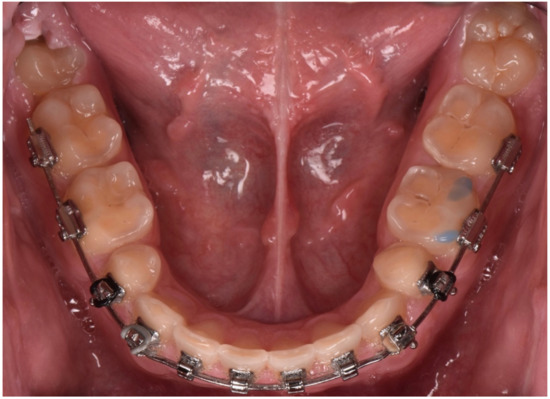

2.2. Restorative Phase